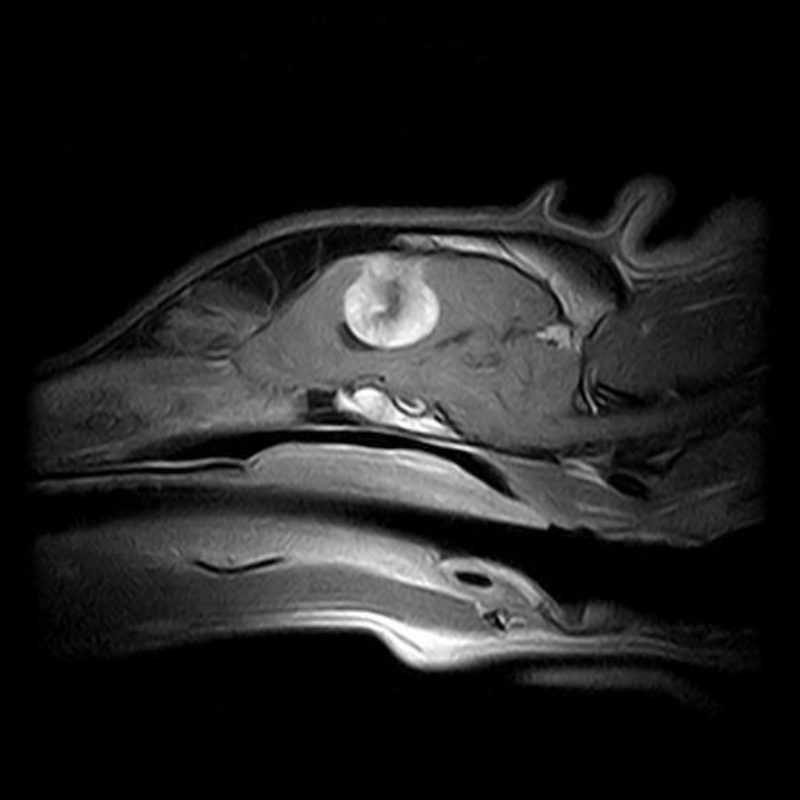

Auch die anschließenden Blut- sowie Urinuntersuchungen waren bei Happy unauffällig. Es bestand daher aufgrund des Alters, der Rasse und der bisher unauffälligen Untersuchungsergebnisse der Verdacht einer idiopathischen Epilepsie. Um diesem Verdacht weiter nachzugehen wurde bei Happy eine MRT-Untersuchung des Gehirns und eine Liquoruntersuchung  durchgeführt, ebenso ohne Befund. Die Verdachtsdiagnose „idiopathische Epilepsie“ stand fest und Happy wurde auf ein Antiepileptikum eingestellt. In den folgenden zwei Jahren traten keine Anfälle mehr auf.